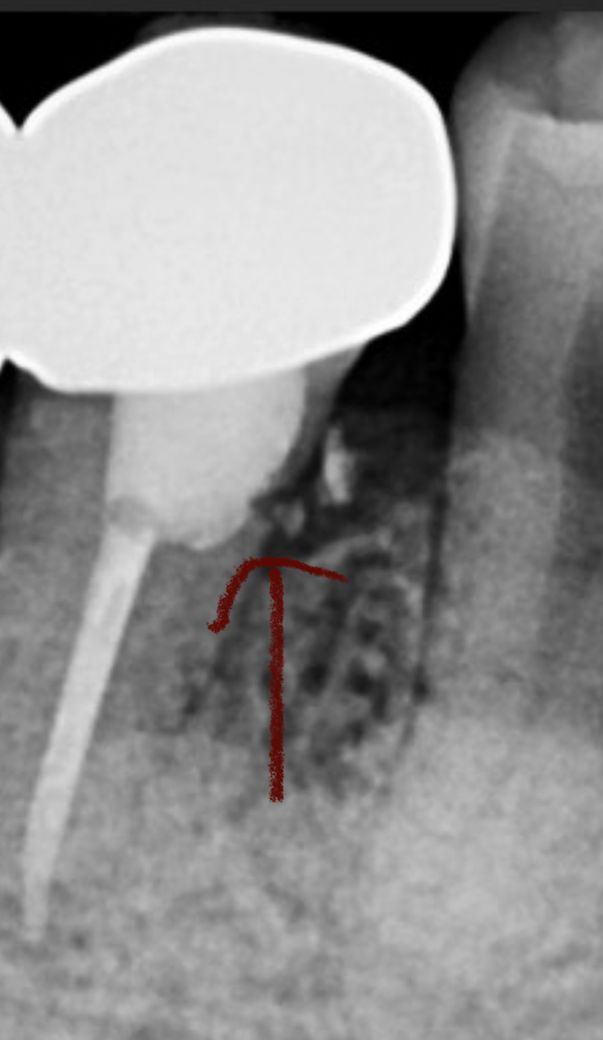

이건 크게 상관 없는 부분인가요??(크라운)

크라운 아래로 이부분은 뭔가 떨어져 나간건가요? 추후 문제 생길 요지가 있나요??

해당 부위는 치조골과 가까운 치아의 뿌리 쪽에 신경 치료나 그 외에 충치료를 하다가 구멍이 난 것으로 보입니다.

해당 부위가 이물질이 들어가게 되면 감염이 되기 때문에 지속적인 문제를 발생할 수 있습니다. 큰 문제가 없다면 그대로 사용하셔도 되며 불편감이 있다면 치료가 필요할수 있습니다.

해당 부위는 잇몸뼈 하방의 치아 뿌리 부위입니다. 만약 충치나 깨진것이라 하더라도 치료가 어렵습니다. 지금 치아에 아무런 증상 없는데 건드리면 득보다 실이 많습니다. 그 충치를 해결하려고 잇몸 째고, 잇몸뼈를 갈아내야 하기 때문입니다.